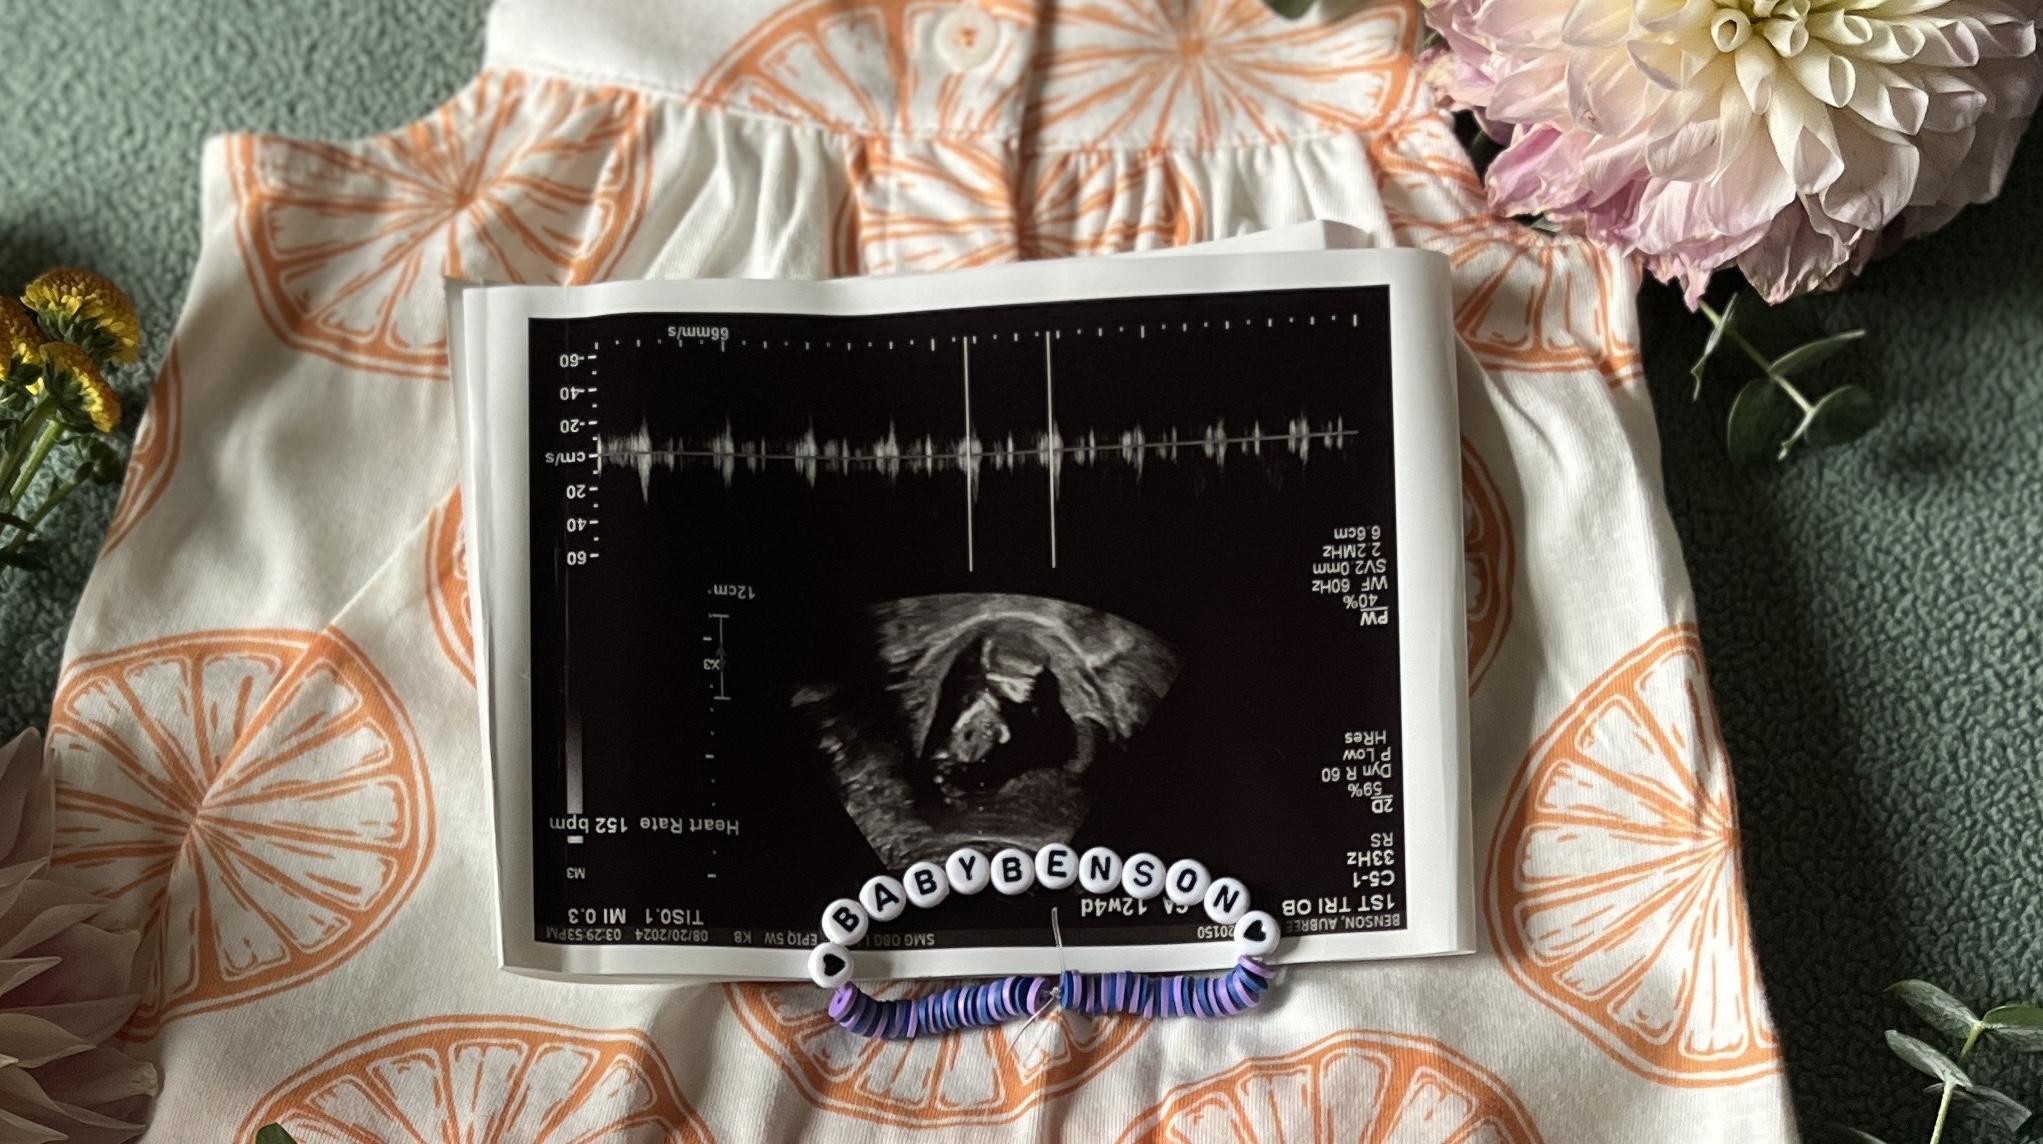

Baby Benson Registry